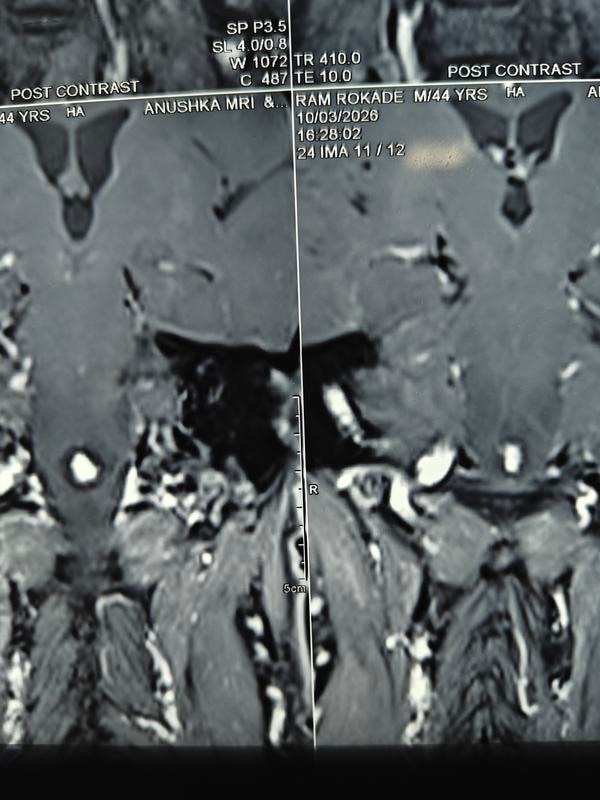

How serious is spinal surgery?Back surgery can carry higher risks than some other types of surgery because it is done closer to the nervous system. The most serious of these risks include paralysis and infections. Even with a successful surgery, the recovery time can be long.